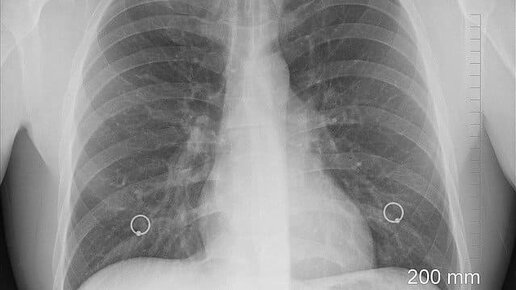

Объём лёгких - точно, легко и просто, способом инженера Шегина.

Что такое объём лёгких?

Этот жизненно важный параметр довольно непостоянен. Например, он может иметь разную величину у двух, казалось бы, похожих друг на друга людей. И даже у одного и того же человека в разные периоды его жизни может фиксироваться разный объём лёгких. Что такое объём лёгких и от чего он зависит? Под нормальным дыхательным объёмом понимают количество воздуха, которое проходит через лёгкие в спокойном состоянии. Эта величина может в несколько раз отличаться от среднего объёма лёгких, который у взрослого человека достигает 4 л...